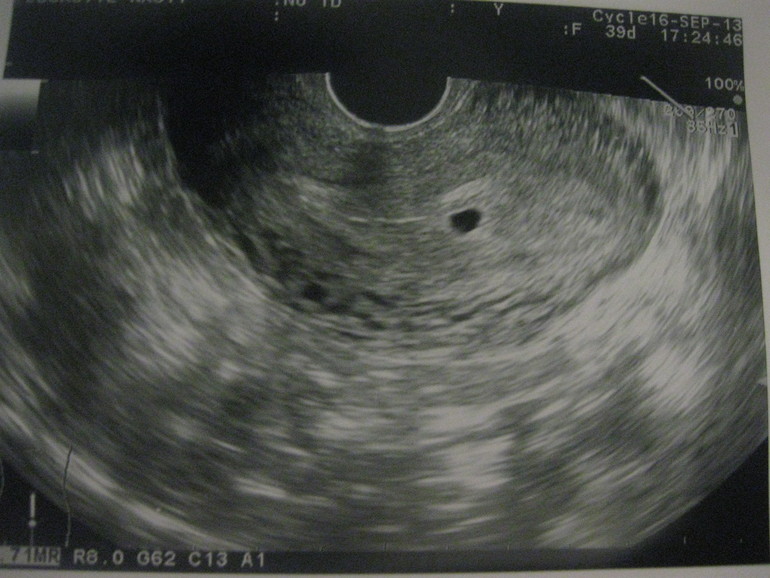

Как только беременность наступила, выявить её никак нельзя, даже посредством ультразвукового исследования (УЗИ). А вот на эндометрий беременность оказывает влияние с самых первых дней. Поэтому, при зачатии, ультразвуковое исследование слизистого слоя с точность укажет врачу на присутствующую беременность даже на самых ранних сроках. Более точную оценку о наступлении зачатия поможет дать анализ крови на содержание в ней гормона ХГЧ. Поскольку именно этот гормон начинает вырабатываться в организме женщины с самого начала оплодотворения яйцеклетки.

В редких случаях бывает, что плодного яйца на УЗИ не видно и количество гормона ХГЧ находится в норме, то есть анализ крови говорит, что беременность не наступила, в такой период врачи и концентрируют свое внимание на состоянии слизистой оболочки матки, выявляя, произошла ли в эндометрии гравидарная реакция или нет. Если да, то врачи констатируют беременность, в результате которой в эндометрии произошли изменения, но эмбрион не закрепился или же был самопроизвольно отторгнут, в результате чего случается выкидыш на ранней стадии зачатия, а значит и не замечен для пациентки.

Как уже говорилось, диагностировать гравидарный эндометрий можно на УЗИ. Более эффективным методом исследования будет трансабдоминальный, нежели трансвагинальный, потому что он, в данном случае, будет более информативным.

Даже если у женщины задержка в один день, то изменения в эндометрии будут четко просматриваться на обследовании. А на 5-8 день отсутствия менструации уже должно быть четко видно наличие либо отсутствие эмбриона. Выходя из этого можно говорить о беременности либо о выкидыше на ранних сроках.